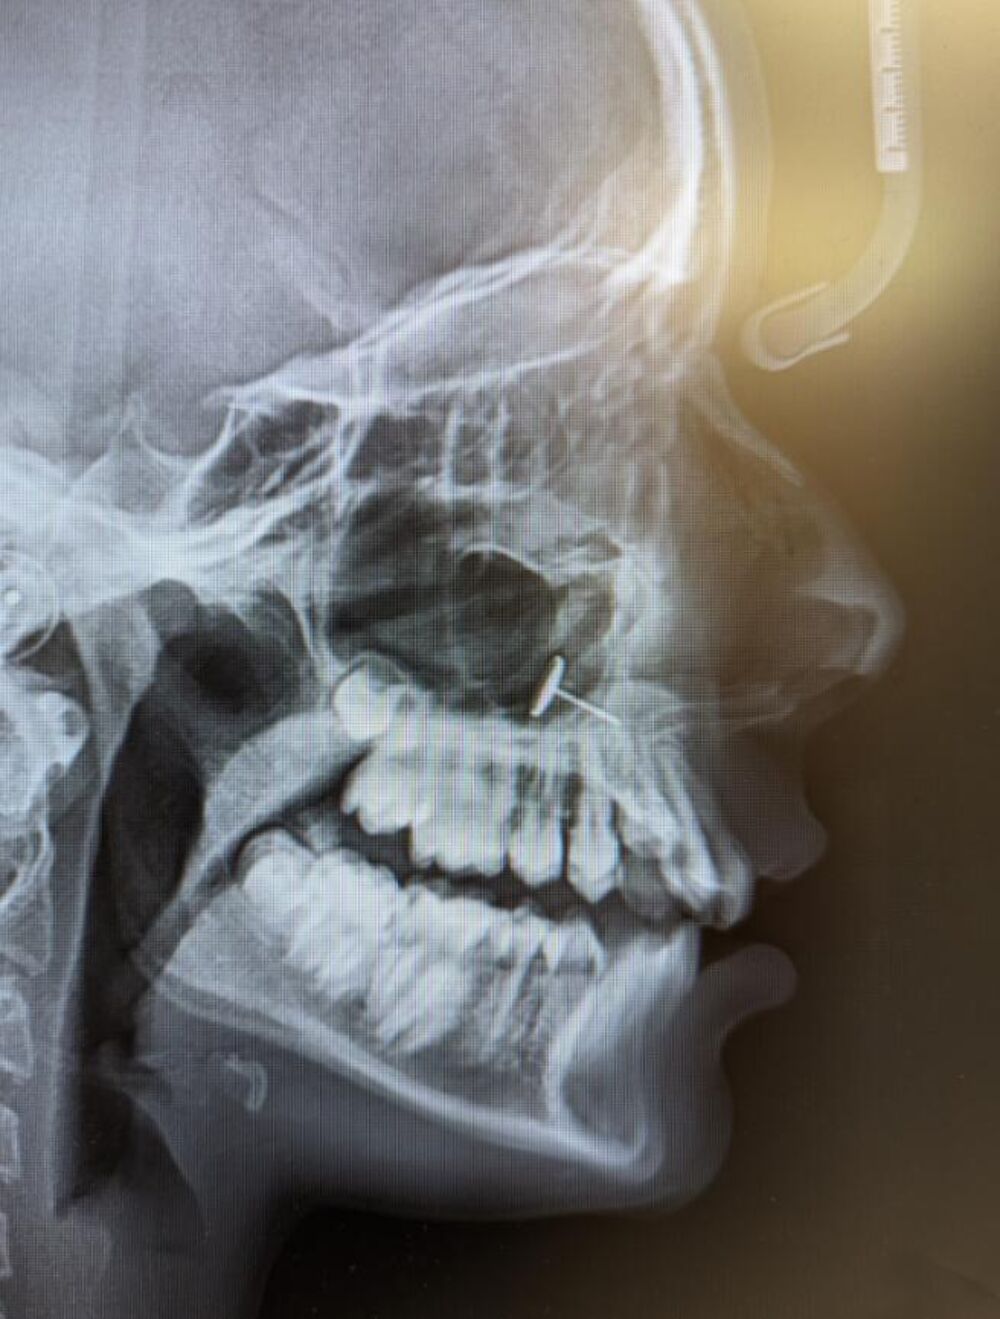

“Zubar se vratio sa rendgenskim snimkom i svi smo nekoliko minuta pokušavali da shvatimo šta gledamo”, rekla je majka

Naime, na snimku se jasno video komad metala zaglavljen u sinusima tinejdžerke(!), ali majka nije umela da objasni kako je tamo dospeo. Istinu je znala devojčica, ali je ćutala.

Sve bi ostalo skriveno, da nije bilo pregleda kod zubara. Majka je objavila rendgenski snimak na Redditu koji je brzo postao viralan.